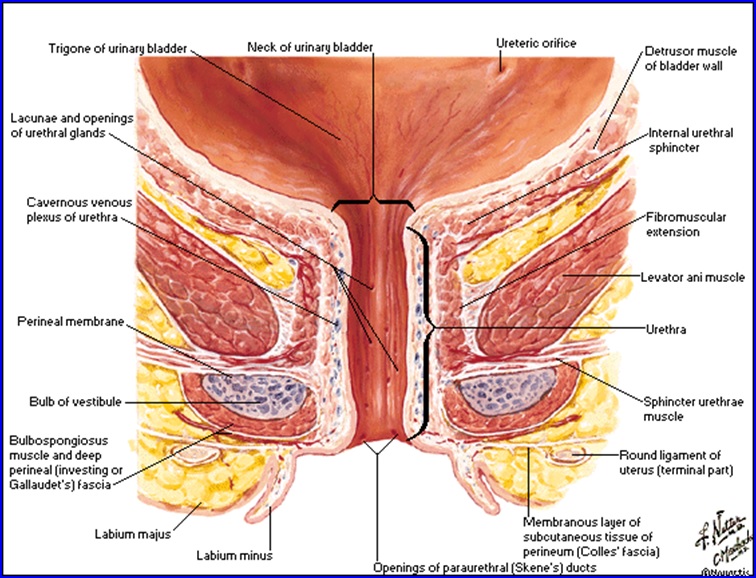

Uretra Feminina

Uretra la femeie, secţiune frontală: